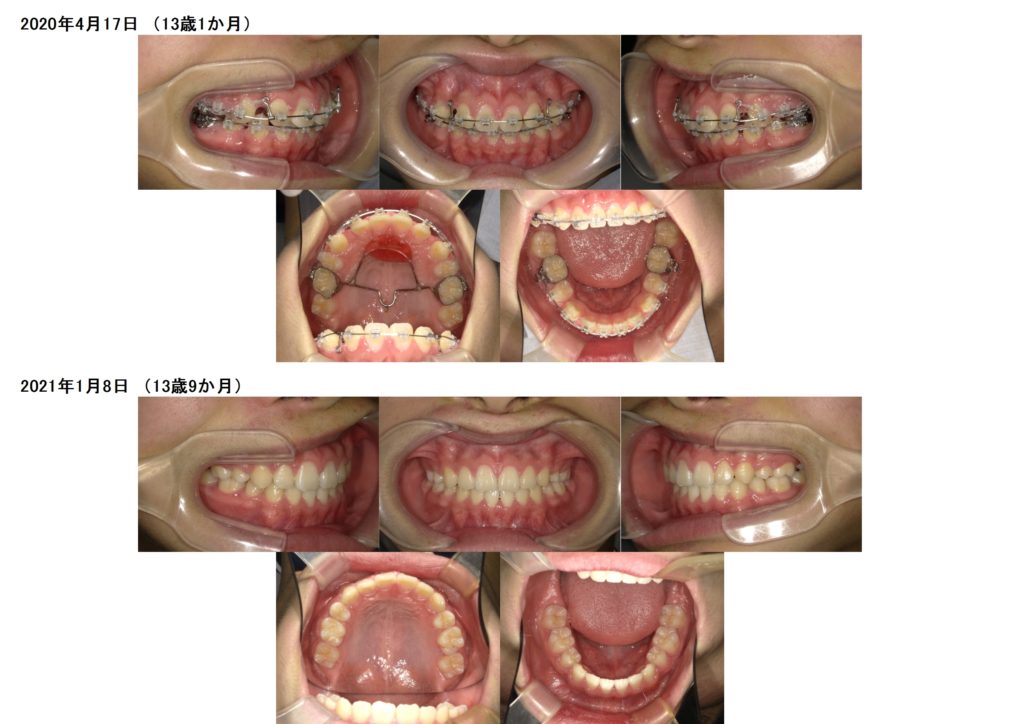

↑治療前、治療後の口腔内写真の比較です。

上下の顎のアーチを整えながら、抜歯した隙間を利用し噛み合わせの深さや突出している部分も改善しているのが分かると思います。

約2年間のブラケット治療になりますが、お口の中もとても変化します。突出している方だと横顔のラインも変わりますので、